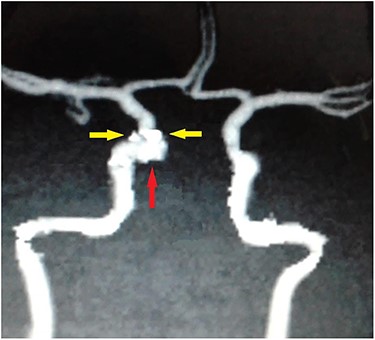

Digital subtraction carotid angiography showing small hyperdense area in the right cavernous carotid artery.

Carotid angiography showing small gun pellets (yellow arrows) and pseudoaneurysm (red arrow) of the right CCA.